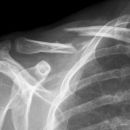

Claviculafraktur im mittleren Drittel